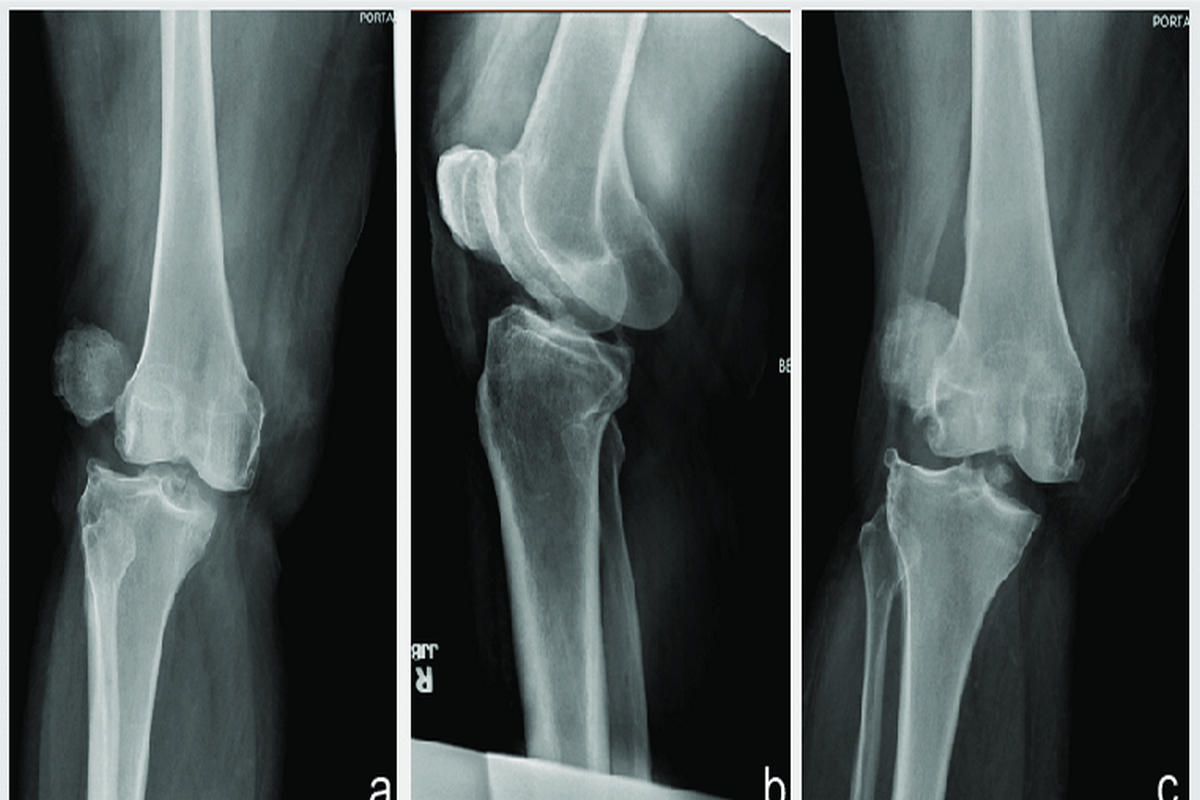

Η διάγνωση βασίζεται αρχικά στην κλινική εξέταση, όπου διαπιστώνεται η παραμόρφωση, η ευαισθησία και το αιμάρθρο. Οι ακτινογραφίες γόνατος είναι απαραίτητες για τον αποκλεισμό καταγμάτων και την εκτίμηση της θέσης της επιγονατίδας.

Η μαγνητική τομογραφία γόνατος αποτελεί σημαντικό διαγνωστικό εργαλείο, καθώς επιτρέπει την αξιολόγηση της ρήξης του έσω επιγονατιδομηριαίου συνδέσμου (MPFL), καθώς και πιθανών χόνδρινων ή οστεοχόνδρινων βλαβών.